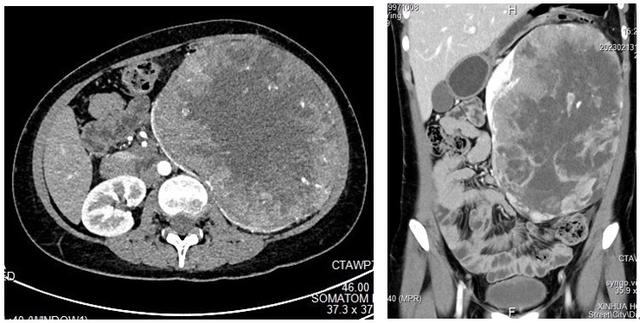

左图:左肾巨大肿瘤 (ct增强横截面)

图片尺寸640x323